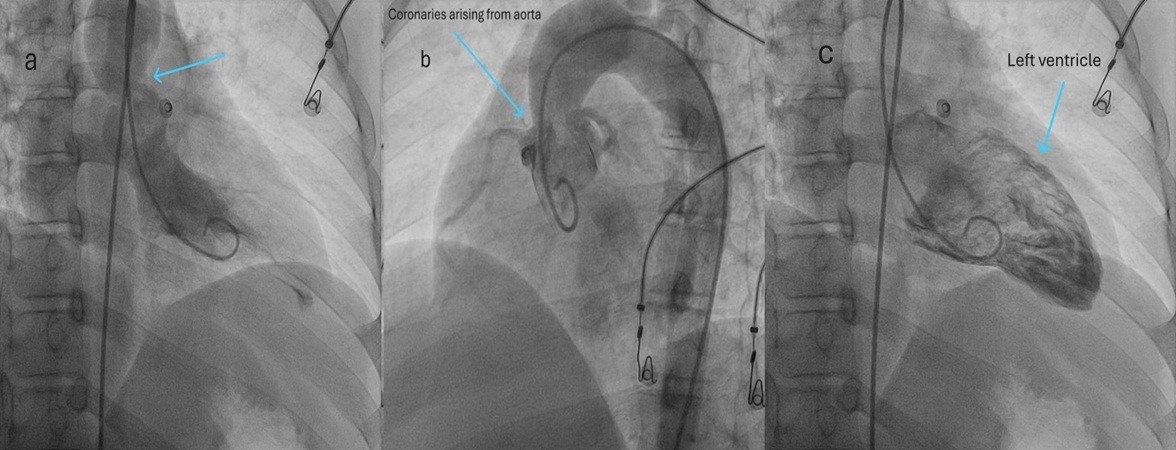

Left ventricular angiogram showed SVAS and normal origin of coronary arteries (Fig. 6).

Figure 5. Cardiac magnetic resonance imaging showing focal narrowing at the supravalvular aortic region (blue arrow) above the aortic valve, consistent with supravalvular aortic stenosis

Figure 6. (a) Systolic left ventricular angiogram demonstrates narrowed supravalvular aortic segment (arrow) consistent with supravalvular aortic stenosis, with pigtail catheter positioned in the ascending aorta; (b) Normal origin of coronary arteries from the aortic root proximal to the stenosis arrow), confirming appropriate coronary anatomy; (c) Left ventriculogram of the left ventricle with preserved cavity outline.